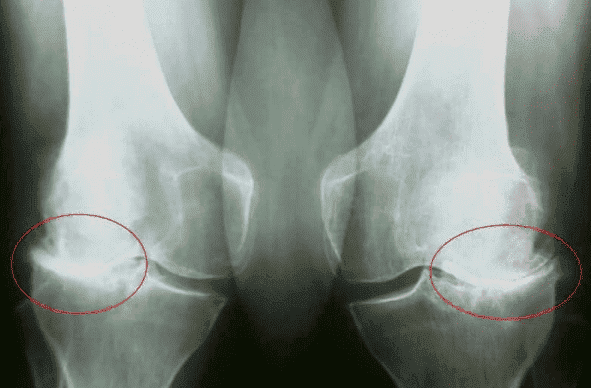

Кореспондент: Какво ти се случи?

Владо Карамазов:

Имам проблеми с коленете, Етап 3 гонартроза. Бях диагностициран преди 5 години. Вината е моя,

защото го оставих настрана. Трябваше да започна да го лекувам по - рано, но всичко, което

направих, беше да взема обезболяващо-не можех да прекъсна снимките, това е нашата работа. Не

обръщайте внимание на болката, трябва да съм на снимачната площадка, иначе ще разочаровам целия

екип.

Владо Карамазов:

Имам проблеми с коленете, Етап 3 гонартроза. Бях диагностициран преди 5 години. Вината е моя,

защото го оставих настрана. Трябваше да започна да го лекувам по - рано, но всичко, което

направих, беше да взема обезболяващо-не можех да прекъсна снимките, това е нашата работа. Не

обръщайте внимание на болката, трябва да съм на снимачната площадка, иначе ще разочаровам целия

екип.

С всеки изминал месец коленете ме боляха все повече и повече. Гърбът също ме болеше. Едва можеше да ходи. Един ден се събудих и не можах да направя крачка. Болеше ме всичко-от коляното до гръбначния стълб. Лекарите казаха, че това е притиснат нерв.

Д-р Кристиян Гоновски:

Да, за съжаление заболяванията на ставите и гръбначния стълб засягат повече от 70% от

населението над 45 години. И след 60 години тази цифра достига 85%! И повечето от тях са виновни за проблемите си!

Д-р Кристиян Гоновски:

Да, за съжаление заболяванията на ставите и гръбначния стълб засягат повече от 70% от

населението над 45 години. И след 60 години тази цифра достига 85%! И повечето от тях са виновни за проблемите си!

Нашите хора, особено възрастните хора, не обичат да се лекуват. Те издържат до момента, в който болката стане непоносима. И когато дойде това време, единственото, което правят, е да използват диклофенак и кеторол.

Искам тези хора да осъзнаят, че хапчетата, инжекциите и други синтетични лекарства са вредни за тяхното здраве. Да, те могат да дадат временен ефект, но ще повлияят негативно на здравето ви след 6-7 седмици.

Инжекциите на болкоуспокояващи (които у нас хората смятат за основен метод за лечение на ставите: диклофенак, кеторол и др.) допринасят за развитието на гастрит и язви, а също така влияят негативно на черния дроб. Хората не осъзнават, че болкоуспокояващите само маскират симптомите, без да решават проблема.

В резултат на това болестта прогресира, разрушавайки ставите и причинявайки непоносима болка.

Физиотерапията, лечението с токове и магнити също няма да дадат желания ефект и могат да се използват само като спомагателни методи.